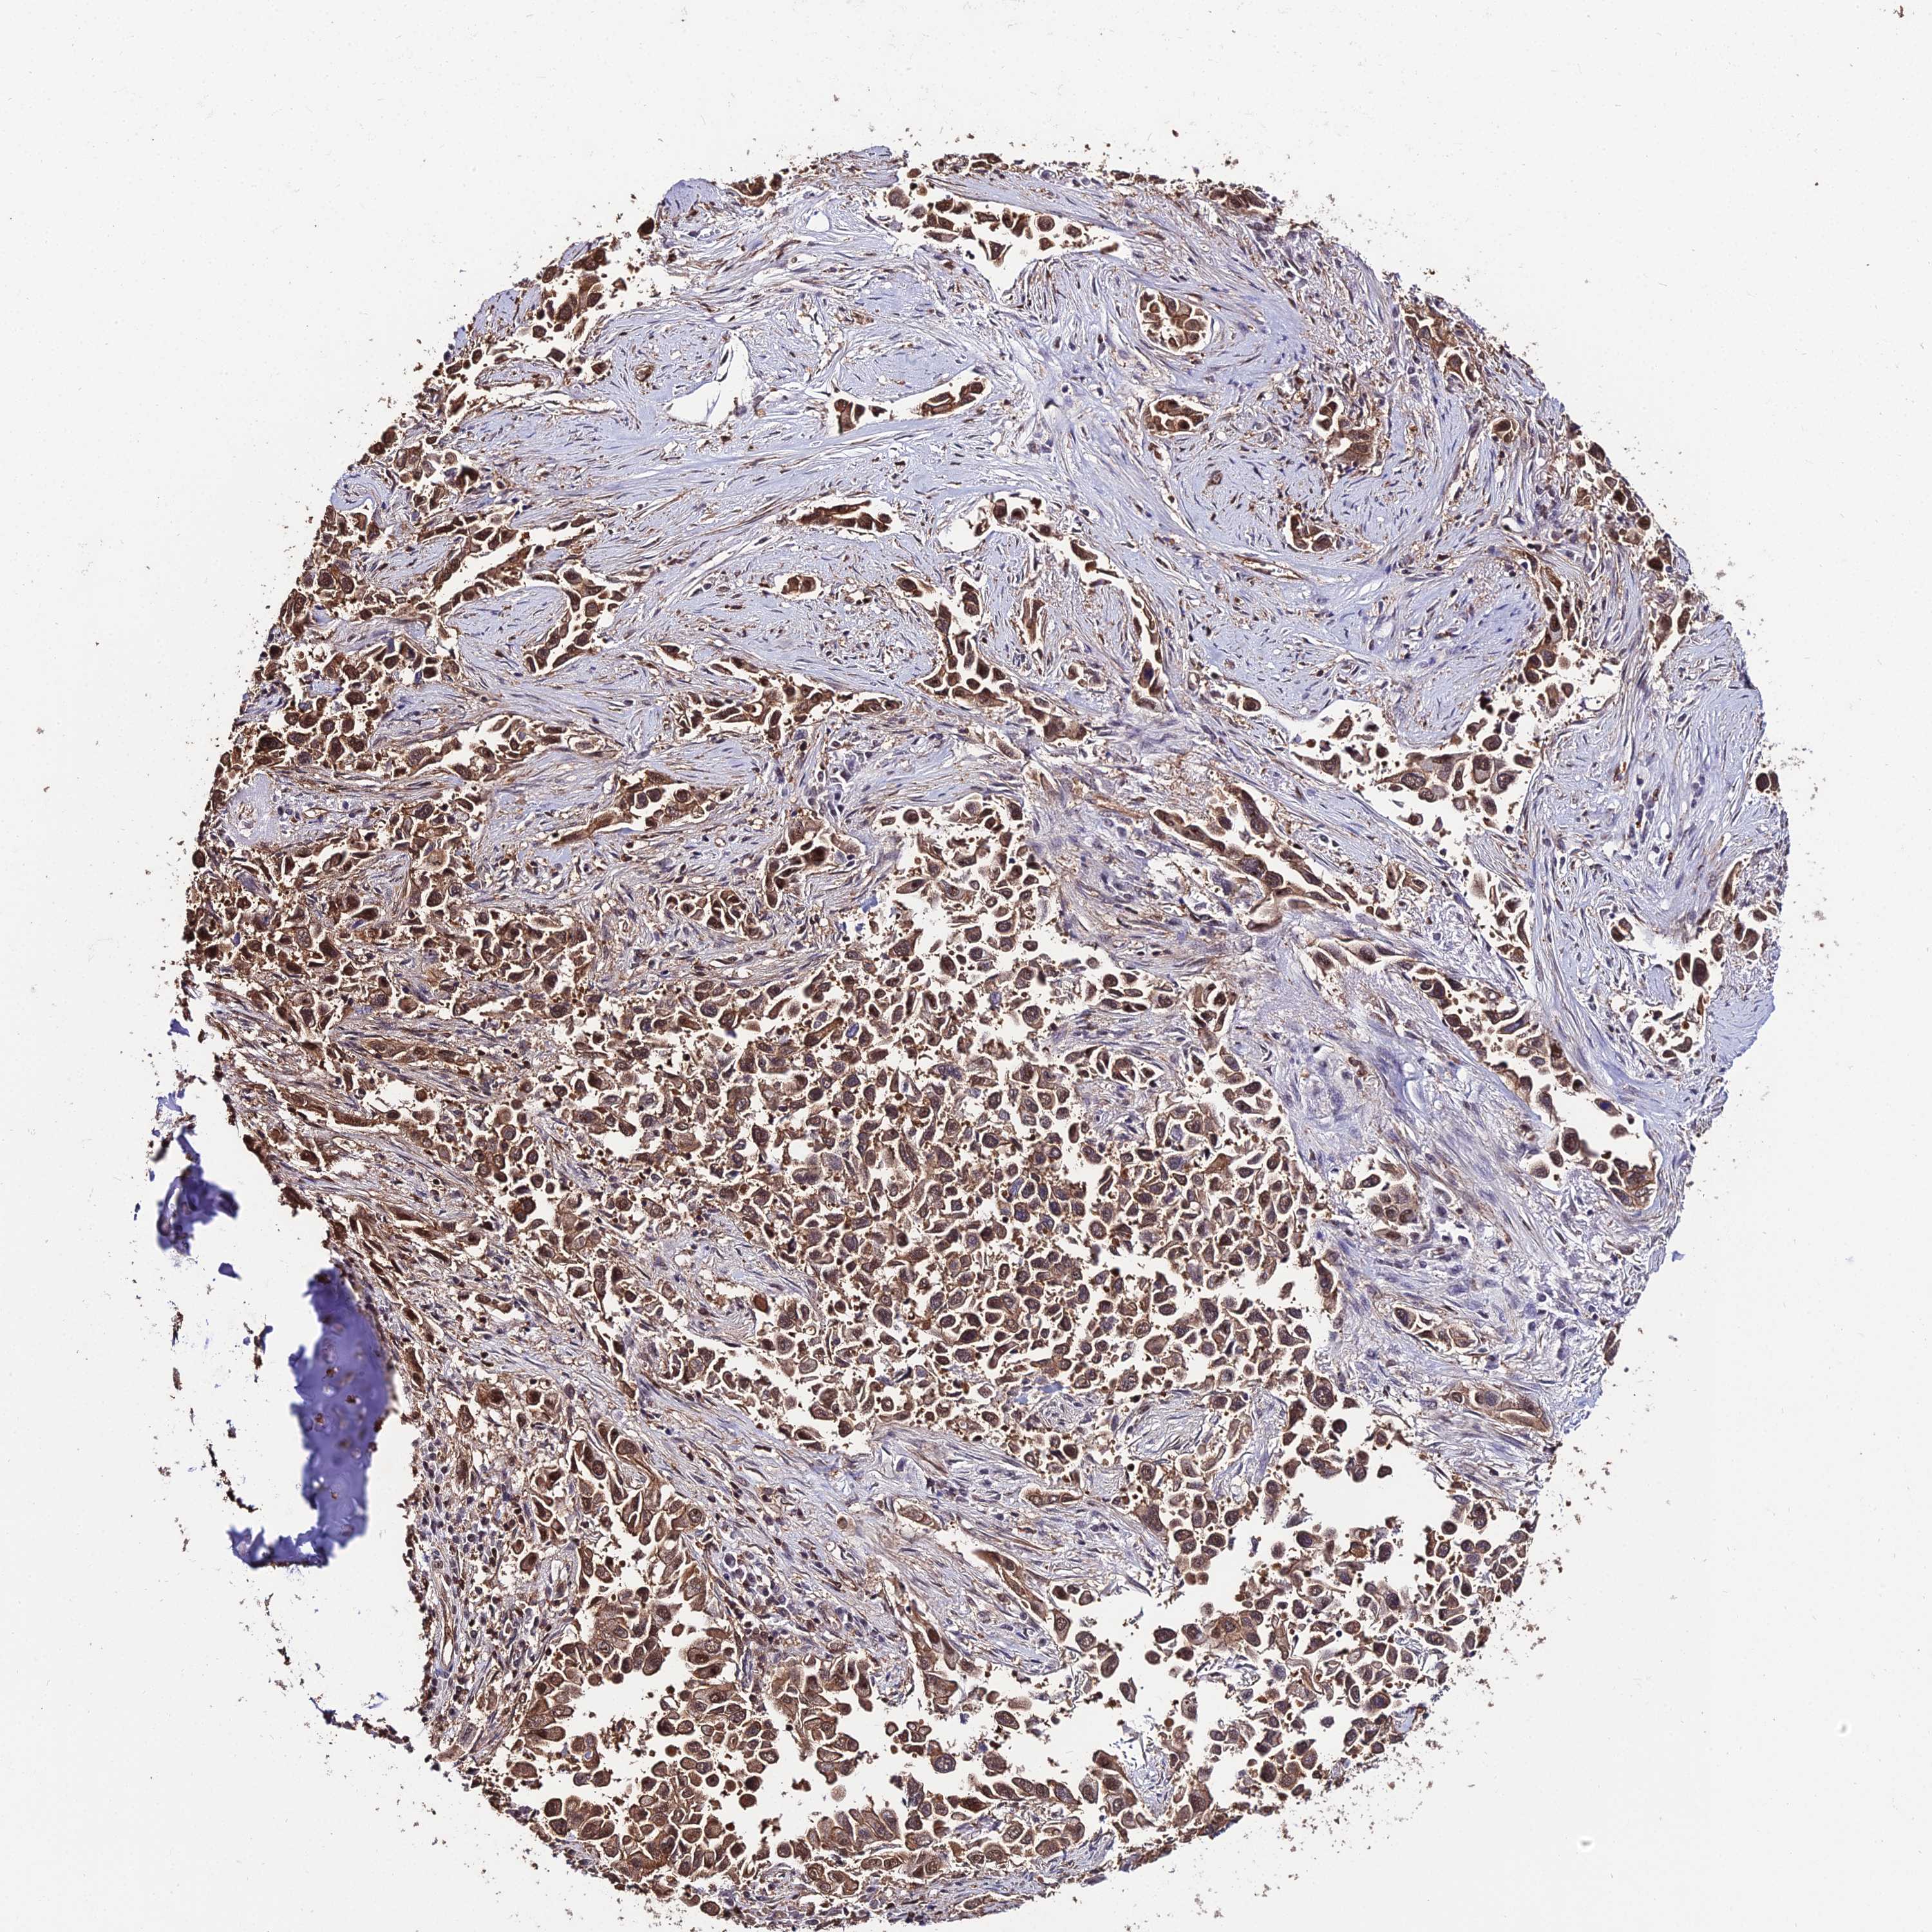

CANCER LUNG CANCER Show tissue menu